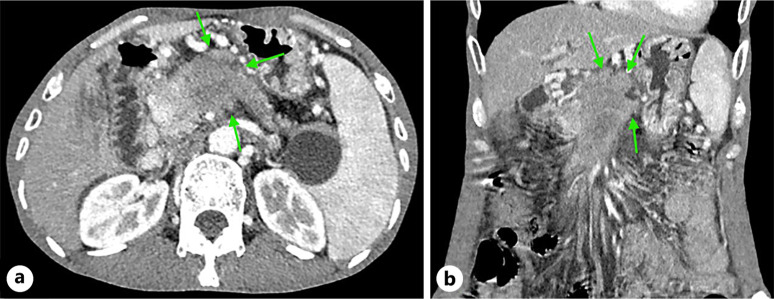

Case presentation: In this case, we report a 57-year-old man who presented with weight loss for 2 months. CT revealed a pancreatic mass. Endoscopic ultrasound biopsy of the pancreatic mass confirmed pancreatic adenocarcinoma. He refused treatment. Eight months later, he developed melena. CT revealed that the pancreatic mass had invaded the gastric wall. Gastric squamous cell carcinoma was confirmed by biopsy of gastric tissue under gastroscopy.